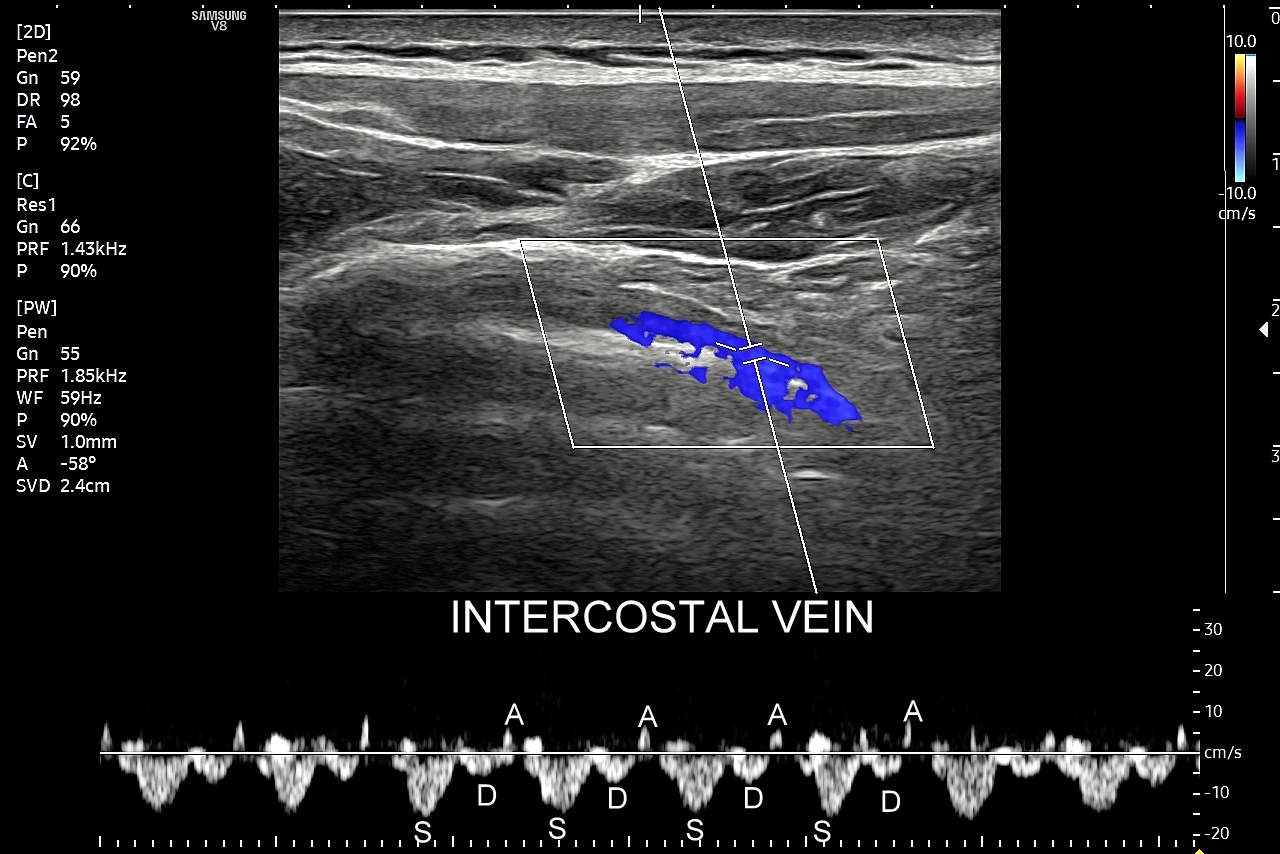

Badanie USG płuc w wybranych przypadkach korzystnie jest połączyć z jednoczesną oceną echokardiograficzną serca oraz dużych naczyń klatki piersiowej, tj. aorty wstępującej i tętnic płucnych. USG układu mięśniowo-szkieletowego klatki piersiowej wykorzystywane jest z kolei w diagnostyce stanów urazowych, takich jak złamanie żeber, czy przeciążenie połączeń chrzęstno-kostnych żeber; w wymienionych przypadkach USG ma wyższą czułość w porównaniu do oceny rentgenowskiej.

Pokrewne badanie USG ścian klatki piersiowej przydatne jest z kolei w diagnostyce stanów urazowych i przeciążeniowych w obrębie układu szkieletowego klatki piersiowej, takich jak złamanie żeber, zespół Tietza, czy naderwanie mięśni. USG klatki piersiowej wykorzystywane jest również przy ocenie zmian guzowatych w powłokach klatki, których przykładami są tłuszczaki, kaszaki, krwiaki, mięsaki i przerzuty nowotworowe.